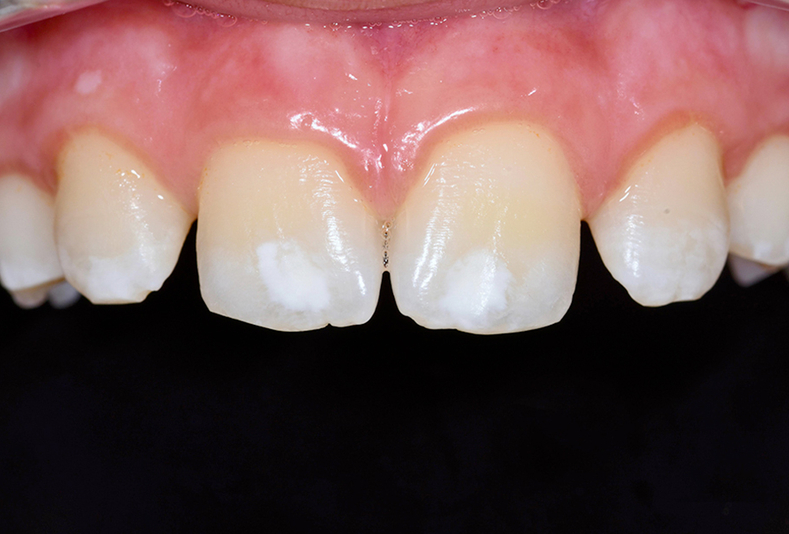

Infiltrazione resinosica per il trattamento non invasivo delle lesioni ipocalcifiche